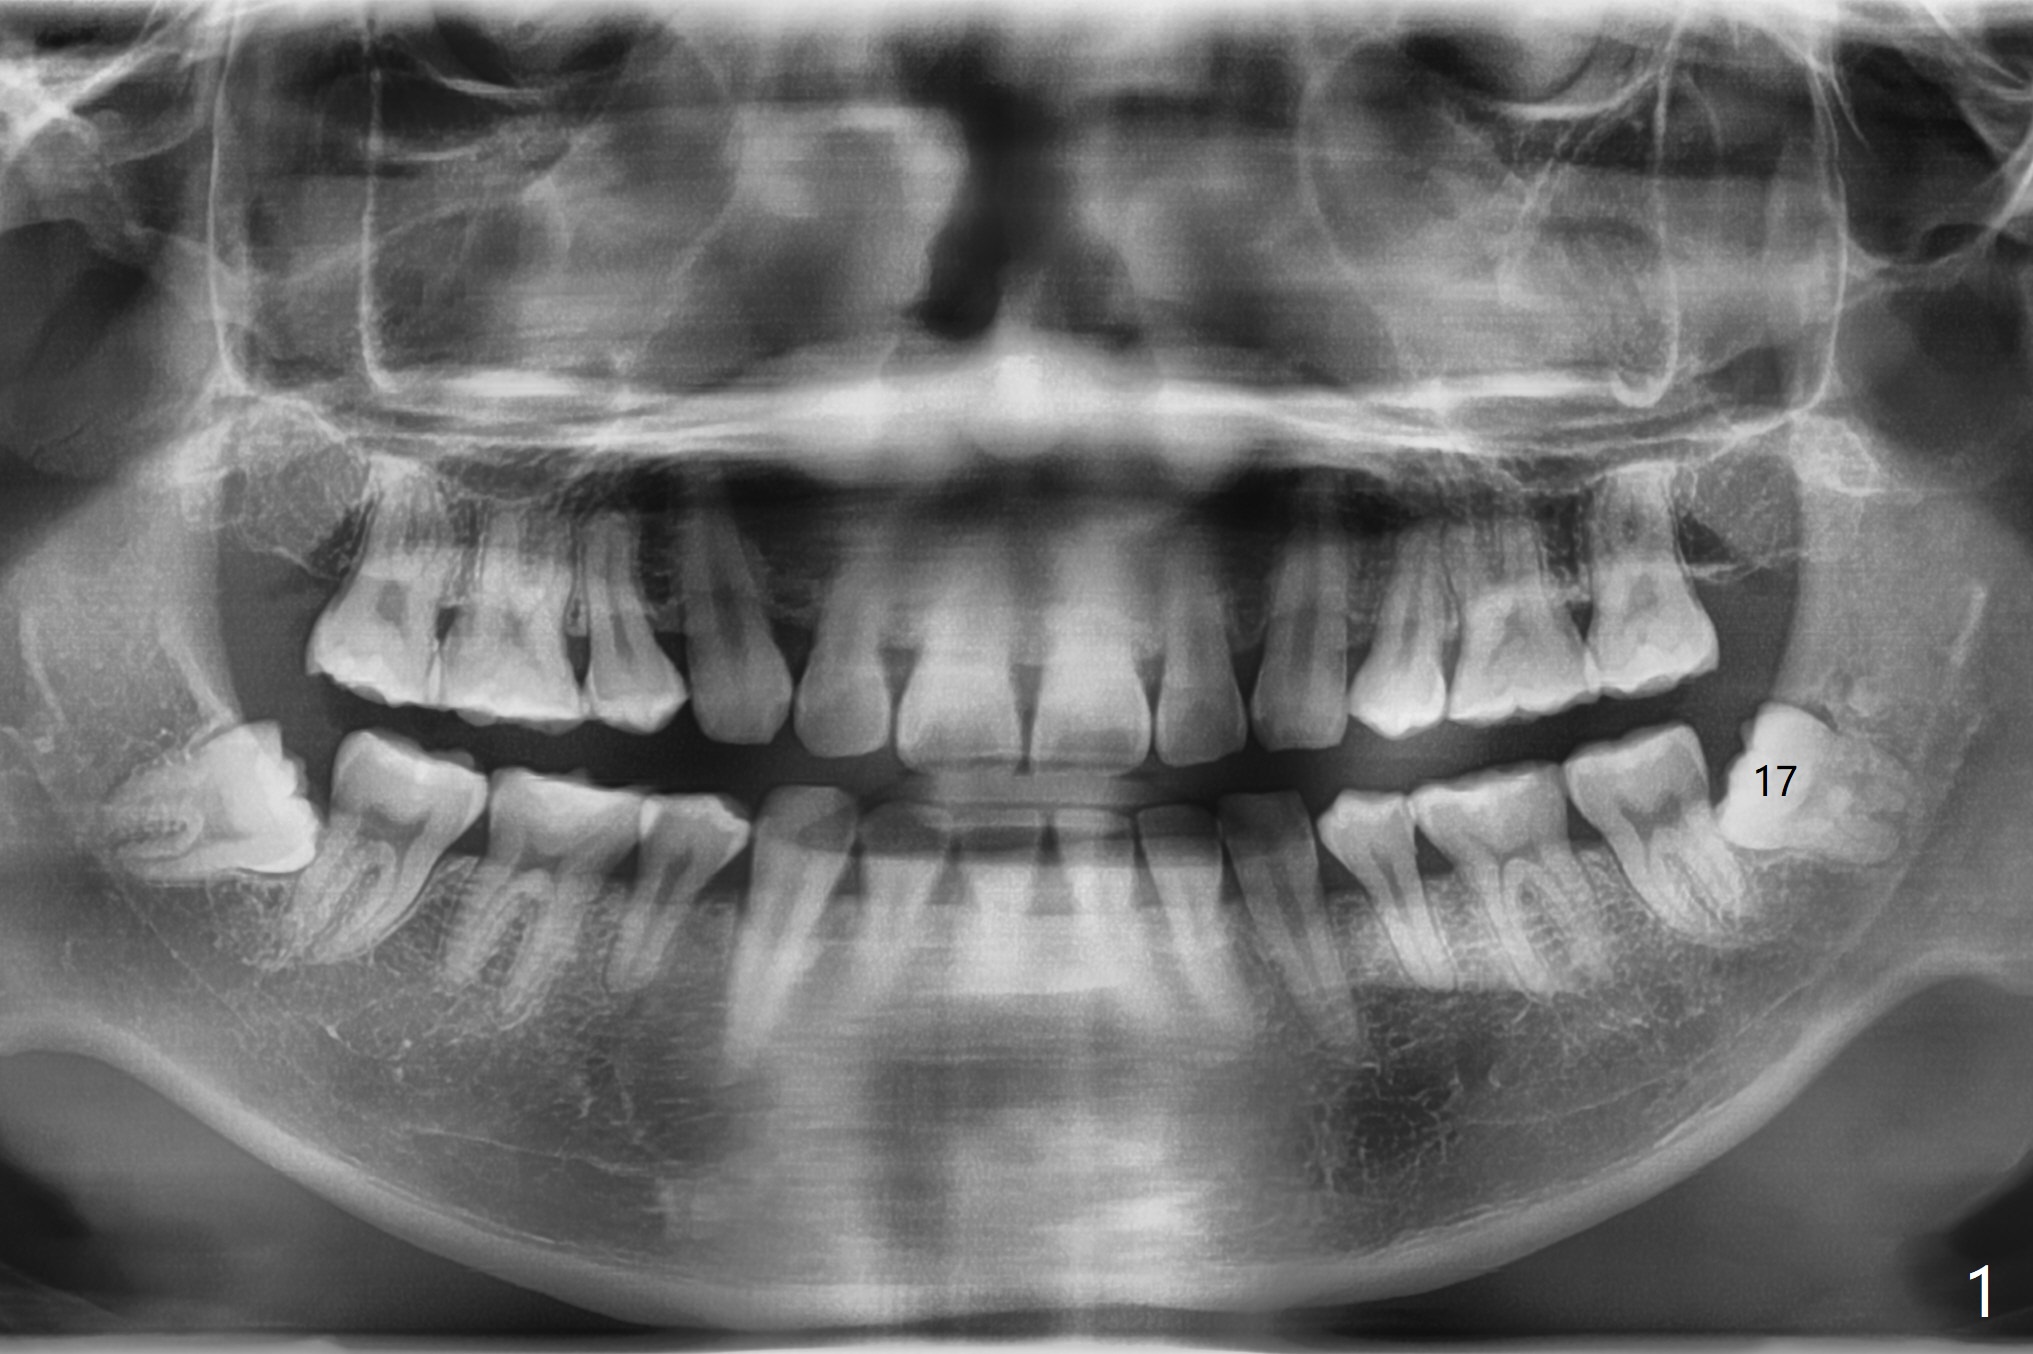

A 27-year-old man requests extraction of the tooth #17. Immediately following 4Q SRP (Fig.1), a midbuccal incision is made (Fig.2 green line) to reduce the chance of graft exposure in case of wound dehiscence because of nearly horizontal impaction of #17. The crown of the latter may be slight mesial to the distal surface of the tooth #18. In fact this is the case after flaps are raised. Since the socket is expected to be large, the graft will be placed immediately distal to the tooth #18 (Fig.2 *), while collagen plug (Fig.3,4 C) will be placed in the root portion of the socket (Fig.2 M, D (mesial and distal)) and in the gingival area (red dashed line to prevent graft material escape). Return to Plug Cement Xin Wei, DDS, PhD, MS 1st edition 06/22/2020, last revision 06/25/2020